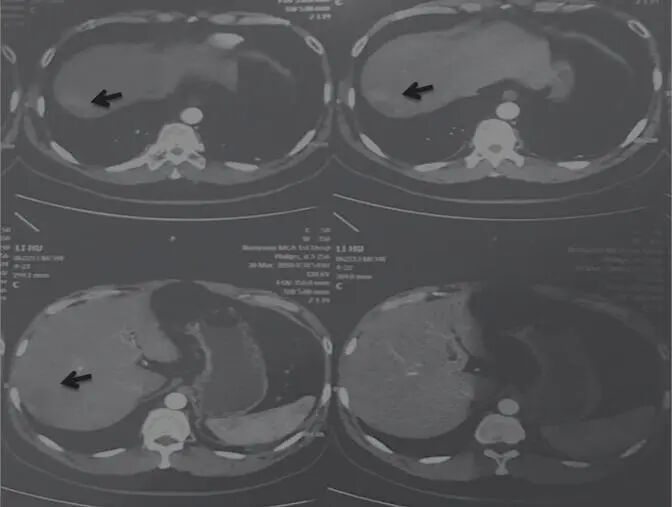

李某,男,32歲,2016年5月14日初診。低熱,口苦,腹脹,尿少,乏力,面色蒼黃晦暗,憔悴神疲,3~5日大便一次,排便困難,舌質(zhì)黯,苔白厚膩,脈弦滑大。

乙肝病史10年,2016年5月7日查AFP 989.8ng/mL,肝右葉巨大占位性病變(圖1),考慮肝癌,大小約15cm×13.2cm,沒有進(jìn)行放療、化療和介入療法。治法:舒少陽,散結(jié)聚,健脾胃,清濕熱,寧心神

圖1 舒達(dá)少陽防治腫瘤驗案初診CT結(jié)果